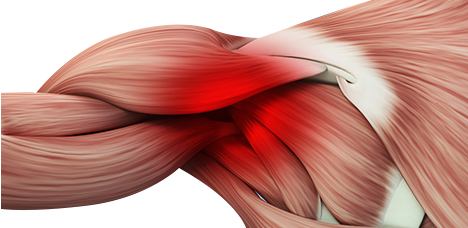

회전근개 손상

어깨회전근 힘줄에 염증이 생긴 질환

이두근 건염

상완이두근의 힘줄에 염증이 생기는 질환